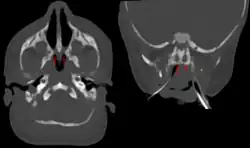

| Bilateral membranous choanal atresia in CT scan | |

Choanal atresia is a congenital disorder where the back of the nasal passage (choana) is blocked, usually by abnormal bony or soft tissue (membranous) due to failed hole development of the nasal fossae during prenatal development. It causes persistent rhinorrhea, and with bilateral choanal atresia, an obstructed airway that can cause cyanosis and hypoxia.

Choanal atresia causes closure of the posterior choanae in the nasal cavity. Around 30% of these affect just the bone, while around 70% affect both bone and membranes. Bones affected can include the body of the sphenoid bone, the vomer, the medial pterygoid process of the sphenoid bone, and the horizontal plate of the palatine bone.[1]

Diagnosis is confirmed using CT scan.[1]This is also useful for differential diagnosis.[1]